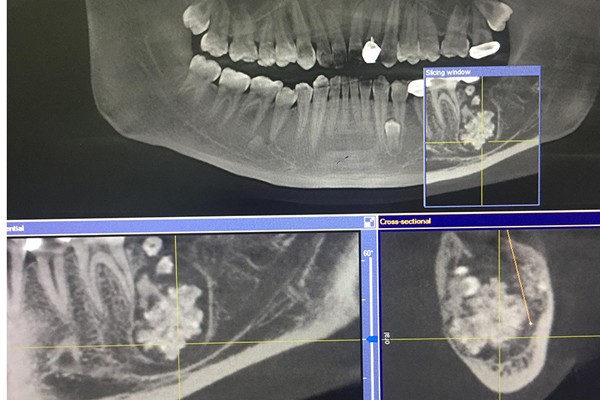

Khi chỉ định chụp X-quang, bác sĩ phát hiện xương hàm dưới có khối u răng kích cỡ 3x4 cm, bên trong chứa nhiều răng to, nhỏ có đầy đủ tổ chức như rằng bình thường, kết lại thành một khối.

BS Đinh Thanh Tùng, khoa Răng Hàm Mặt chia sẻ, ca phẫu thuật kéo dài hơn 1 tiếng. Do khối u nằm sâu, chiếm gần hết thân xương hàm, bám dính chắc vào xương hàm nên bác sĩ phải dùng dụng cụ bóc tách, cắt nhỏ từng phần để lấy ra, tránh tổn thương dây thần kinh.